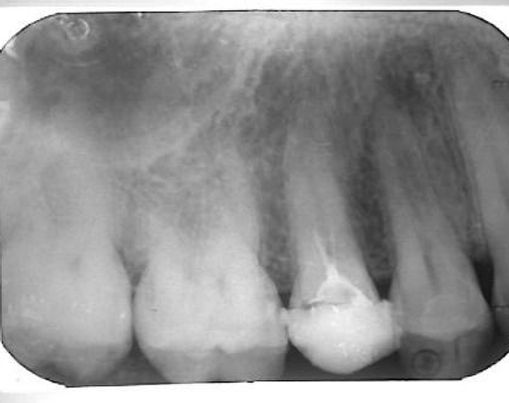

סתימת שורש מורכבת מחומר משכתי וחומר מוצק שנקרא גוטה פרקה.

במהלך סתימת השורש, הגוטה פרקה עלולה לחדור מעבר לקצה השורש.

במצב שבו נדרש לבצע חידוש טיפול שורש בשן, והגוטה פרקה חדרה מעבר לקצה השורש, רצוי להוציאה.

במקרים אלו יש חשיבות לטכניקה ועדינות הטיפול.